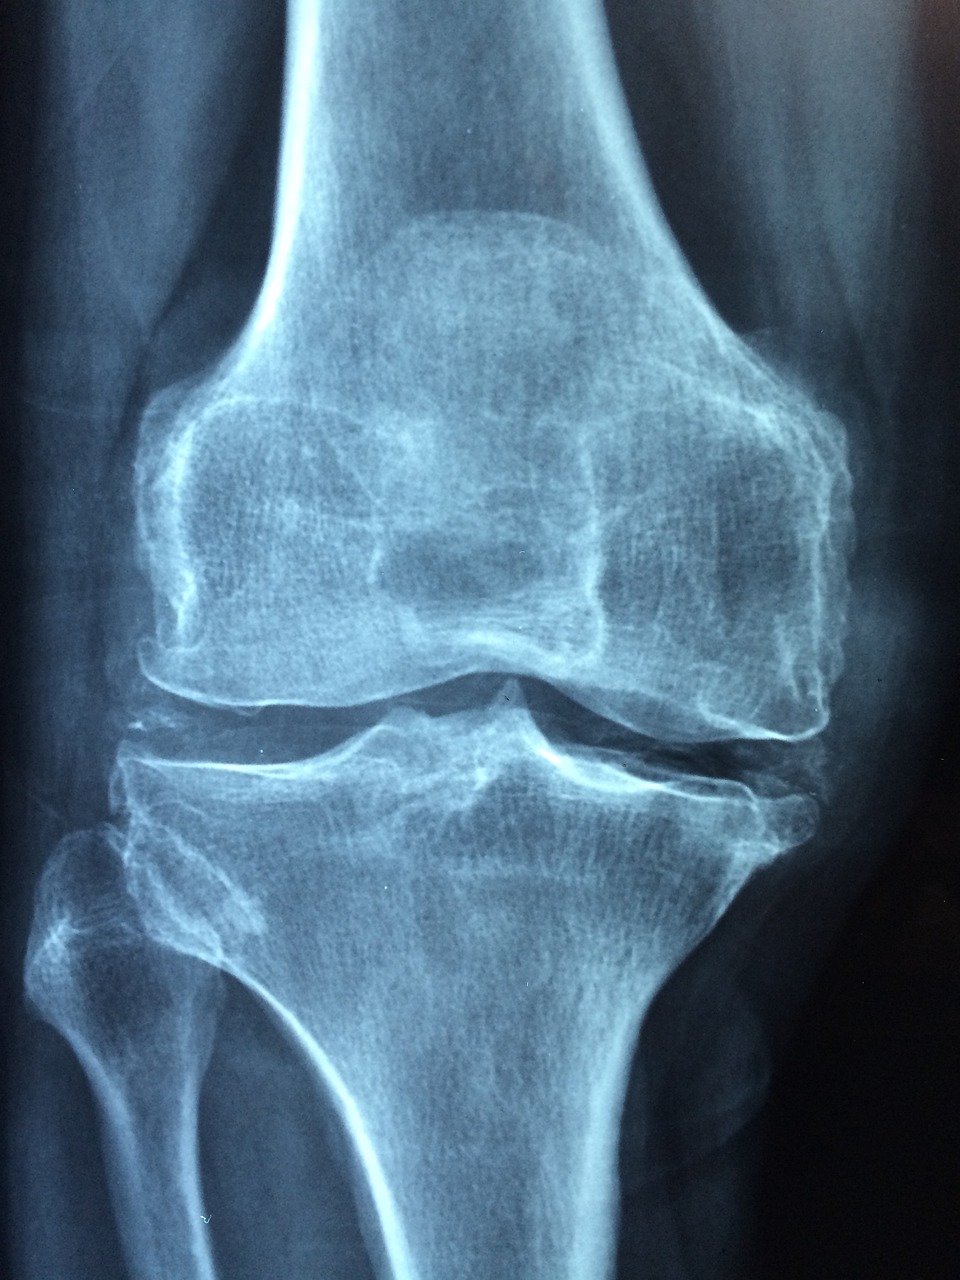

Avant de s’aventurer vers la chirurgie, il est important de faire quelques examens pour voir ce qui se passe vraiment avec votre genou. Les radiographies sont d’une grande aide ici, permettant aux médecins d’évaluer le degré d’usure de l’articulation. Si le cartilage est abîmé ou détruit, ils vous recommanderont probablement une intervention chirurgicale.

La taille et le type de la prothèse sont des aspects essentiels à prendre en compte. Chaque genou est unique, et il est nécessaire que les pièces prothétiques soient adaptées à votre morphologie. Cela se fait généralement à l’aide de calques sur les radiographies préopératoires. Un bon orthopédiste s’assurera également que le matériau utilisé pour la prothèse est de qualité, garantissant ainsi la durabilité et la résistance de l’implant.